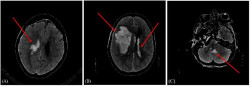

La Fundación Centro de Investigación de Enfermedades Neurológicas (CIEN), dependiente del Instituto de Salud Carlos III y respaldada por la Fundación Reina Sofía, avanza en el diagnóstico preciso del Alzheimer mediante biomarcadores sanguíneos y ha confirmado la conexión entre los niveles en sangre de la proteína fibrilar glial ácida (GFAP, por sus siglas en inglés) y el desarrollo de la enfermedad, estableciendo por primera vez en humanos la relación entre esta proteína y la activación de los astrocitos en el cerebro, clave en los procesos inflamatorios de la patología.